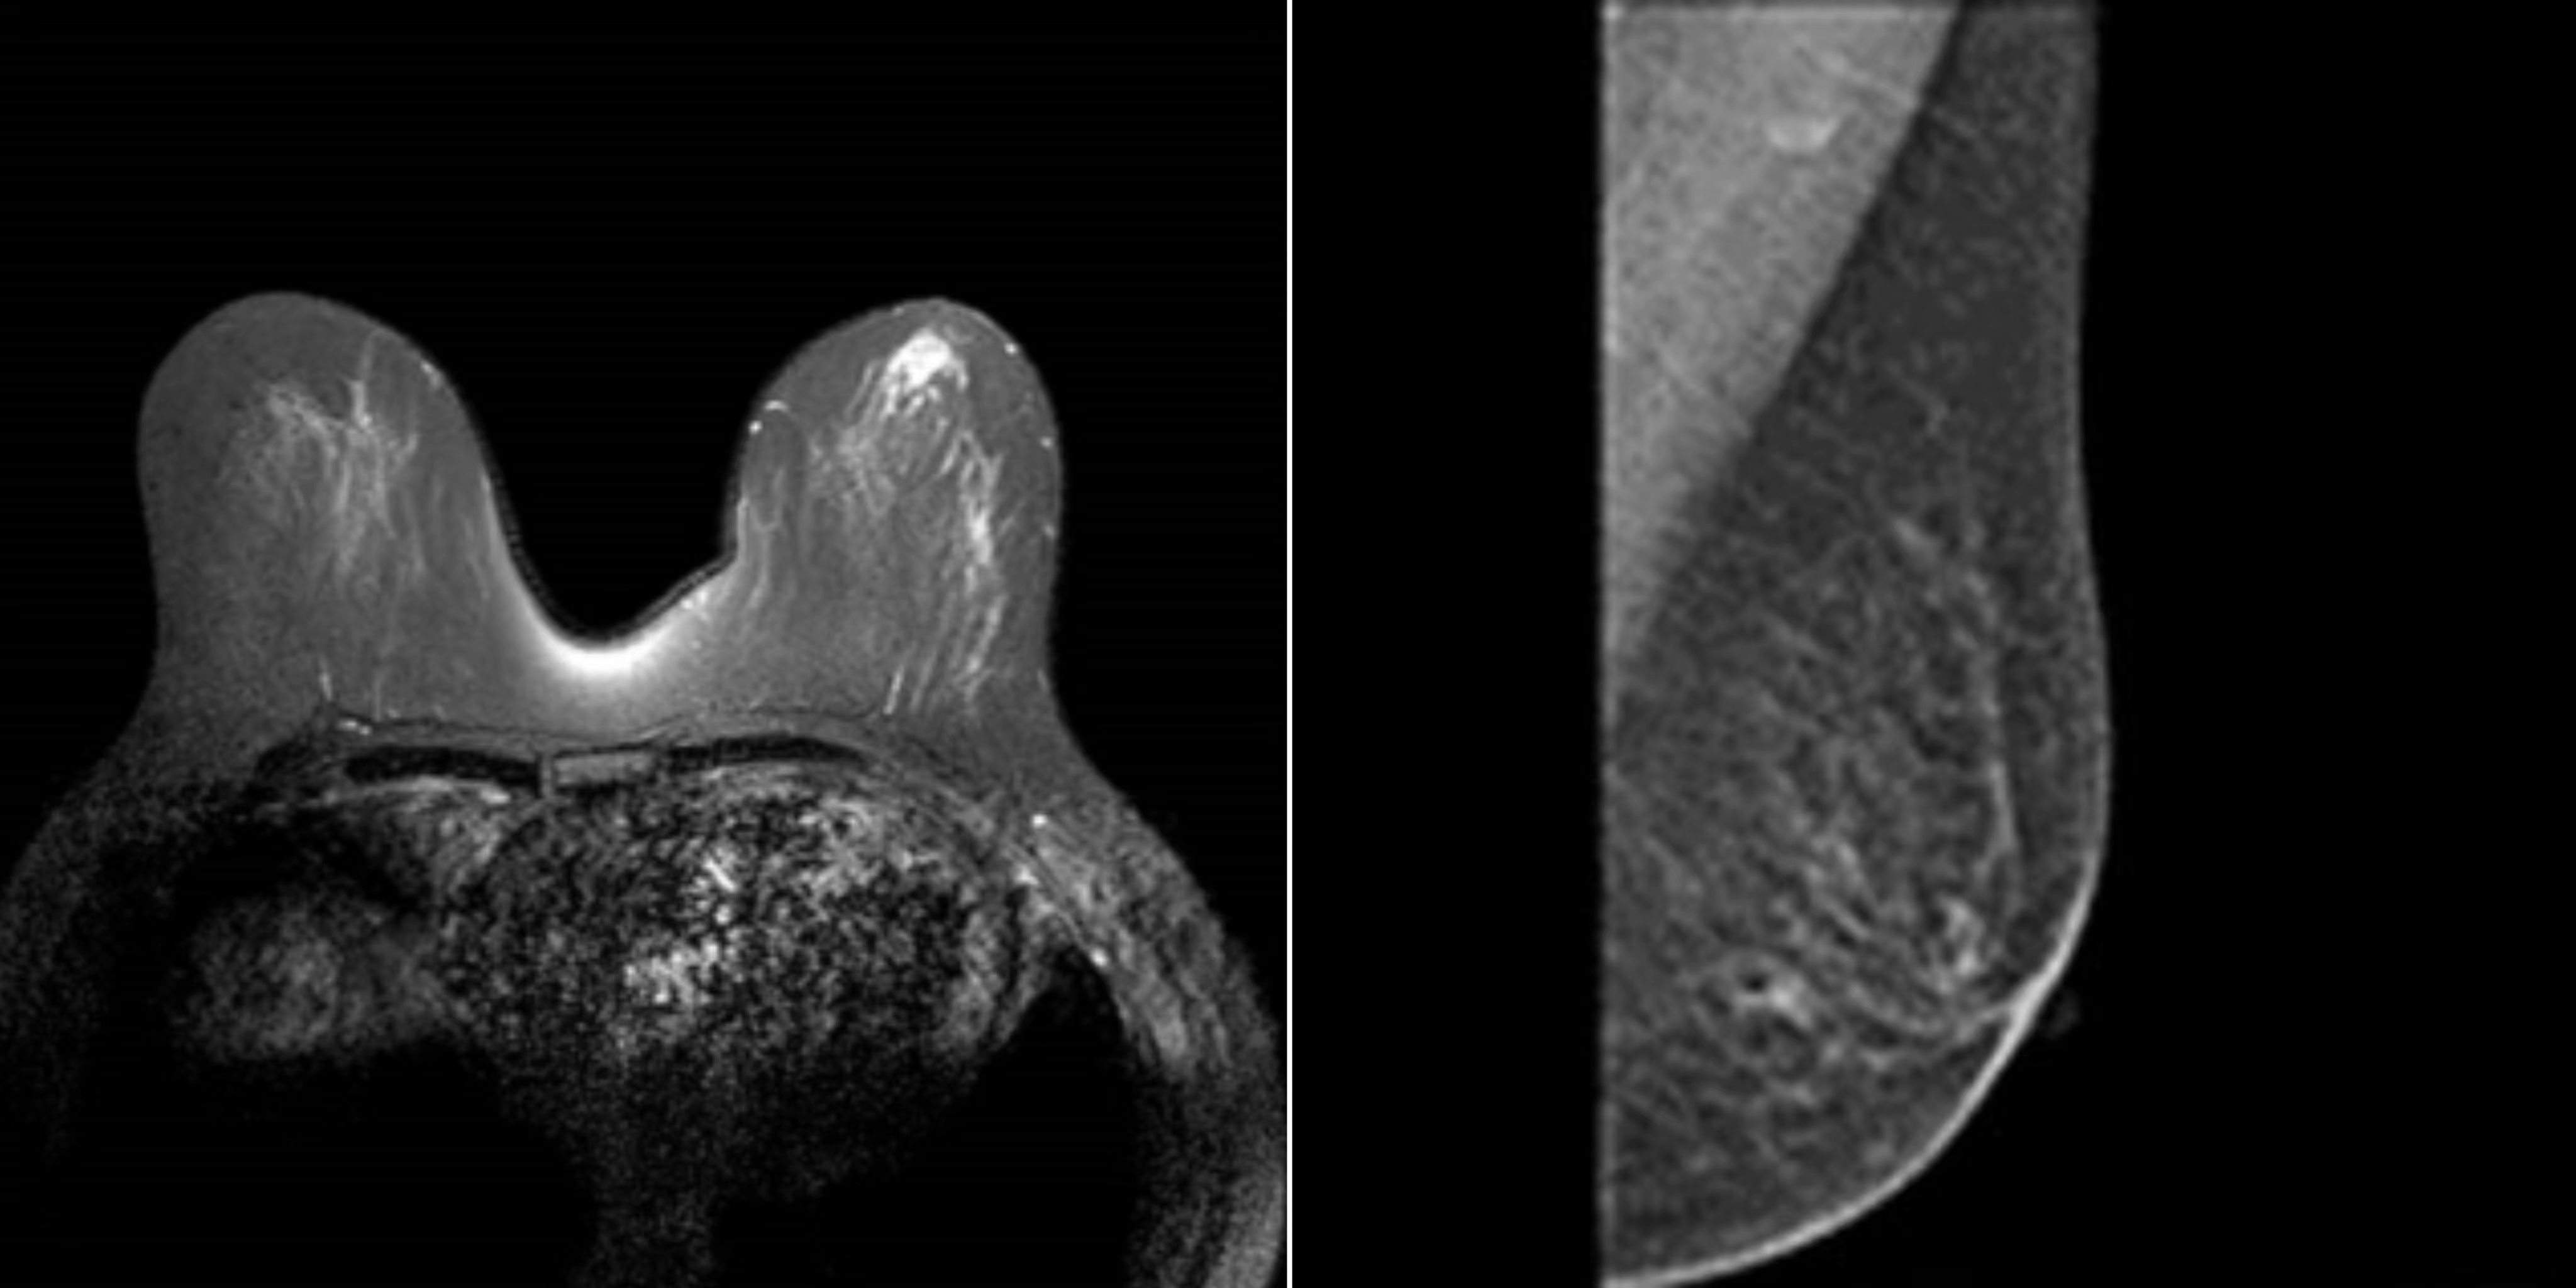

近日,色情导航 乳腺外一科副主任崔舜瑀教授团队成功施行东北三省首例达芬奇机器人下经腋窝单孔全腔镜乳腺癌改良根治术。标志着色情导航 乳腺外科进入达芬奇机器人高端精准新时代,为更多乳腺患者带来了新的希望。

67岁的患者郭女士,因“右乳肿物”入院。经查双乳房表面皮肤无红肿破溃,无卫星结节,右侧乳房有2个肿物分别与不同象限,2x2cm,两个乳腺肿物均是恶性肿瘤。根据CACA-CBCS(2022版)指南、以及考虑患者本身年龄及病情,不适合保留乳房手术。但郭女士对切口的长度及位置有强烈的要求及意愿。经乳腺外一科团队会诊,并与家属充分沟通后,最终选择此术式。

52岁的患者佟女士,因“左乳肿物”入院。经查双乳房表面皮肤无红肿破溃,无卫星结节,左侧乳房肿物2x2cm。腋下淋巴结肿大融合2x2cm,给予系统治疗后。此次入院检查适合手术。根据CACA-CBCS(2022版)指南、以及考虑患者本身年龄及病情,不适合保留乳房手术。

崔舜瑀教授带领团队在术前进行了充分的病情分析、术前切口的标记与测量,依照两位女士的意愿,为她们量身定制了个性化的手术方式和预案准备。术中,团队使用自制的“乳腺单孔腔内镜戳卡”进行操作,1例采用“逐层法”切除全部腺体并完整保留乳头乳晕。1例采用“逐层法”切除全部腺体及乳头乳晕,手术过程十分顺利。目前患者切口愈合良好,术区无任何异常,无不良反应及并发症,此术式在避免术后放疗的同时,兼顾健康和美观,且“无痕”,患者及家属表示非常满意,并顺利出院。

术后,崔舜瑀教授表示,该术式的主要亮点一是通过达芬奇机器人灵活的机器手及超清晰3D成像技术达到更精细的手术操作,既能解决肿瘤治疗又能最大限度减少损害,满足患者对健康和美的双重需求;二是应用前哨淋巴结活检切口施行单孔建腔使其切口更加隐蔽,解决了乳房表面切口带来的皮瓣坏死、积液等术后并发症的风险,规避了患者胀痛不适等缺点,实现了乳房表面无痕化的美容效果,而且保留胸大肌的功能不受影响,改善乳房形态。